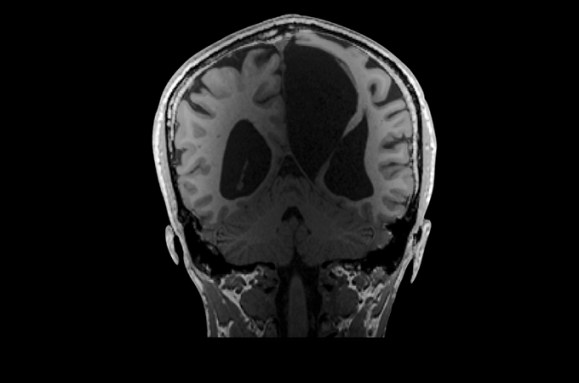

As of May 30, the Interesting Brains Project had scanned the brains of 30 people. Some have holes in their frontal or temporal lobes; others are missing parts of their cerebellum, a brain structure involved in balance and movement. Still other participants have brain matter that’s squished up against the sides of their skull; scans show voids that appear to have ballooned from the brain’s center.

Hydrocephalus has left its mark in K.V.’s brain, pushing neural tissue toward the sides of their skull and pressing the cortex thin. K.V.’s ventricles, cavities filled with cerebrospinal fluid (center), are larger than most people’s and form a fluid-filled void in the center of the brain. K.V. makes their living as a writer. COURTESY OF THE FEDORENKO LAB -